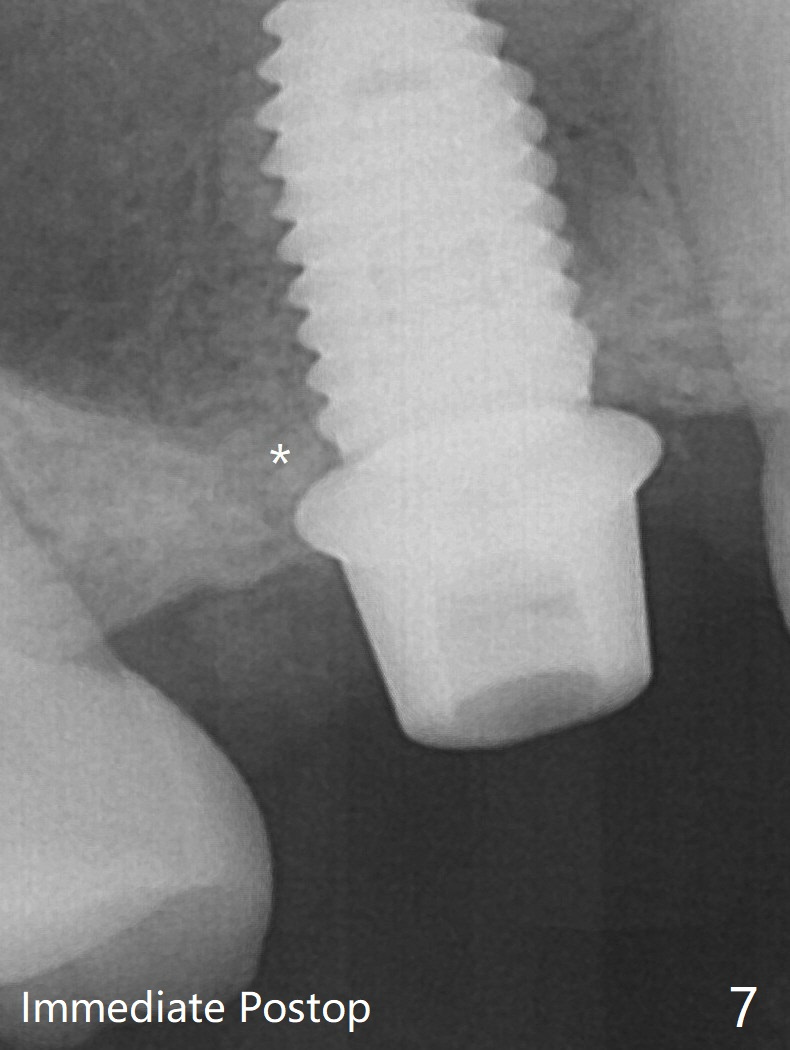

A 4.5x10 mm dummy implant is placed with high torque after 4x7.3 mm drill with 3 mm stopper so that 4.5x7.3 mm drill with 1 mm stopper is used before placement of a 5x8.5 mm final implant with ~ 35 Ncm (Fig.6-7). There is no pain when a 5.2x4(2) mm cemented abutment is torqued at 30-35 Ncm before impression (Fig.8). *: bone graft in the sinus. When the permanent crown is delivered, the patient feels light pain when she bites hard. The discomfort persists 4 months post cementation (Fig.9). The crown/abutment is replaced with a healing abutment (Fig.10).